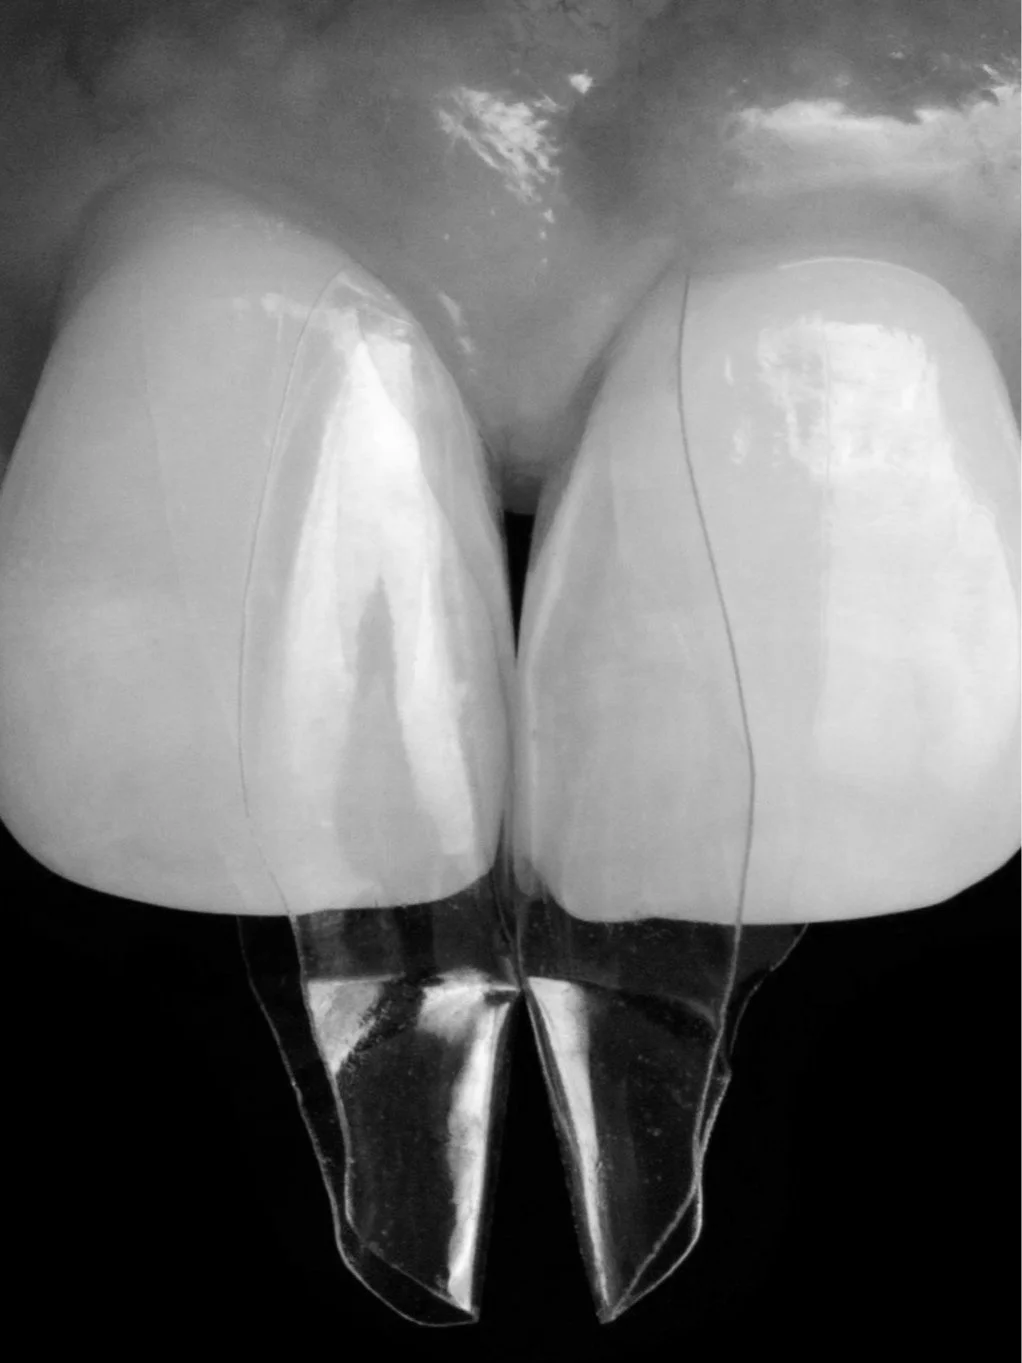

Master the injection overmolding technique to close black triangles with a patient-centered outcome